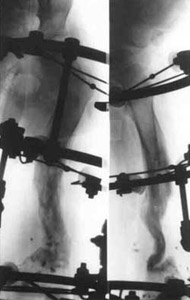

After operation.After operation.

After operation.